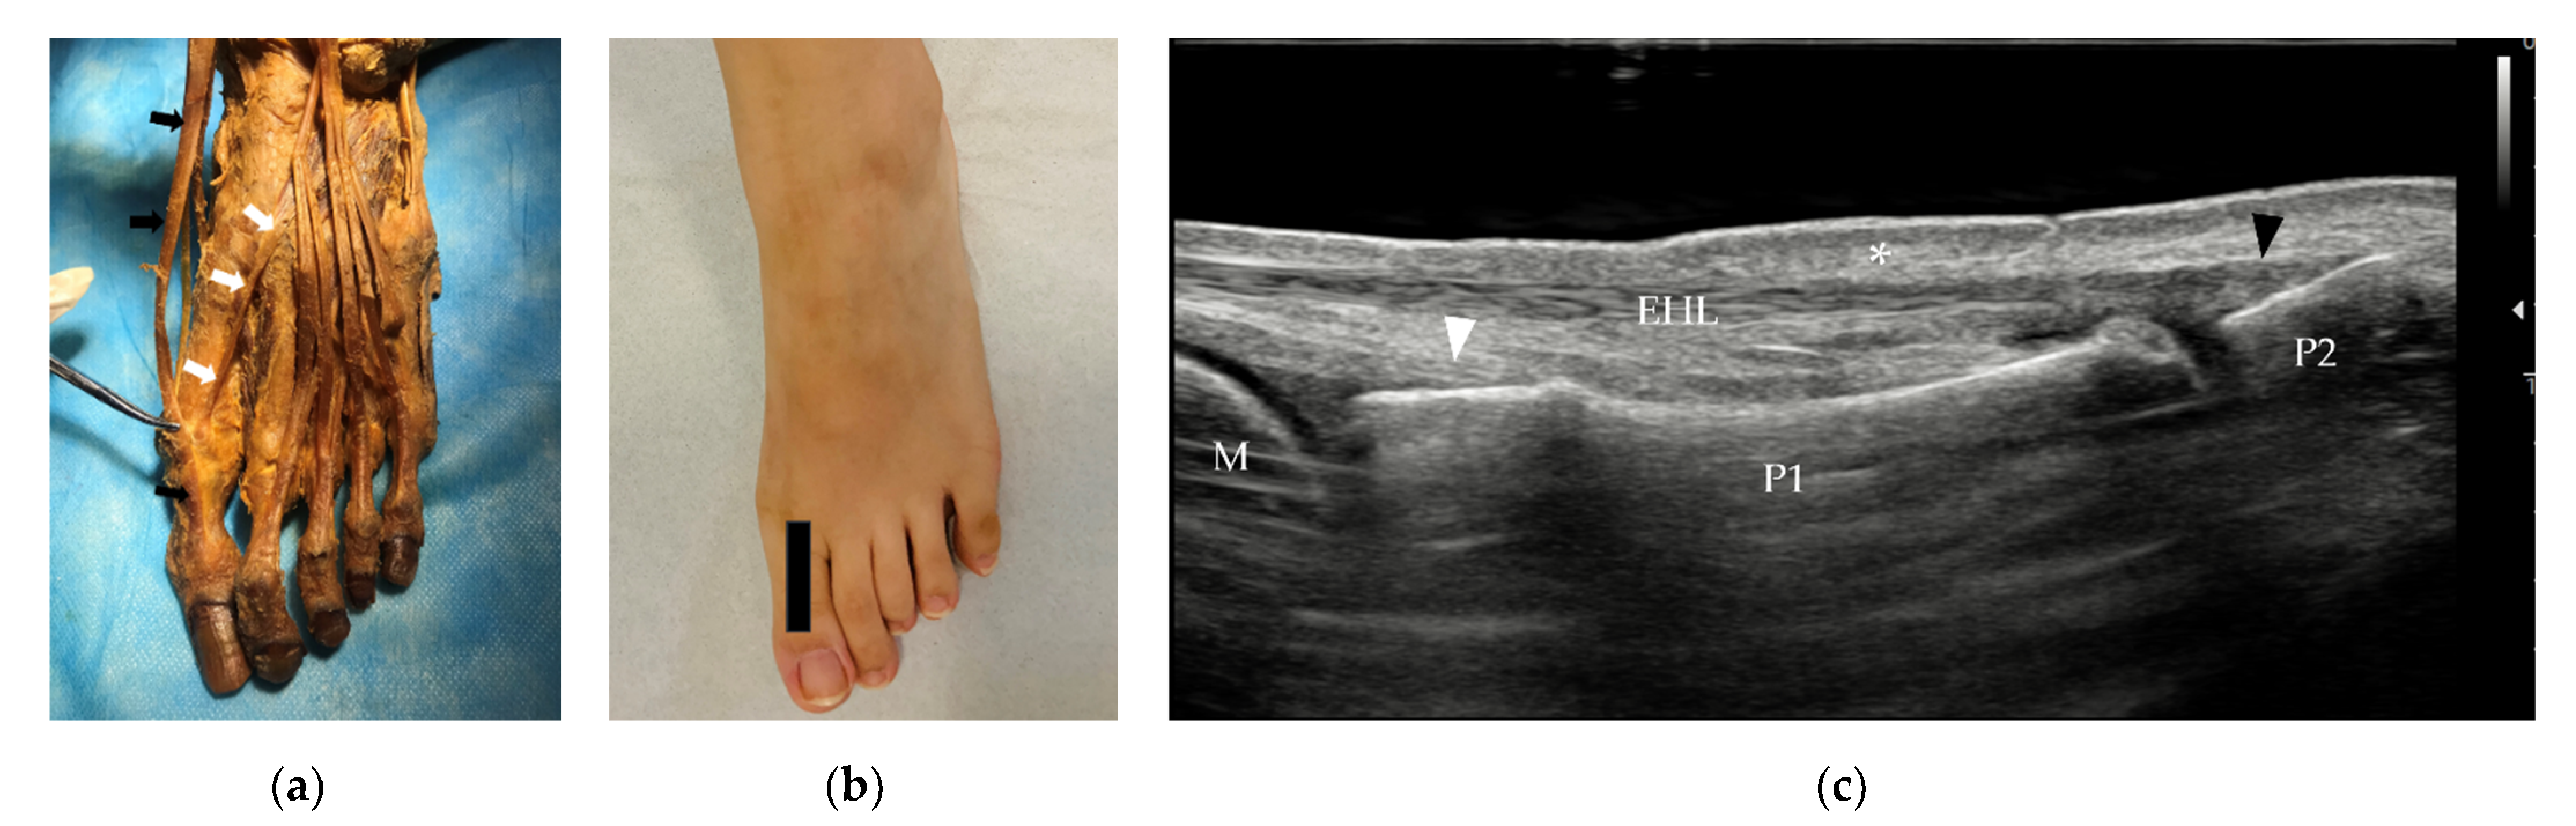

3.2.1. Tendons and Muscles of the Dorsal Foot

3.2.2. Tendons and Muscles of the Plantar Foot